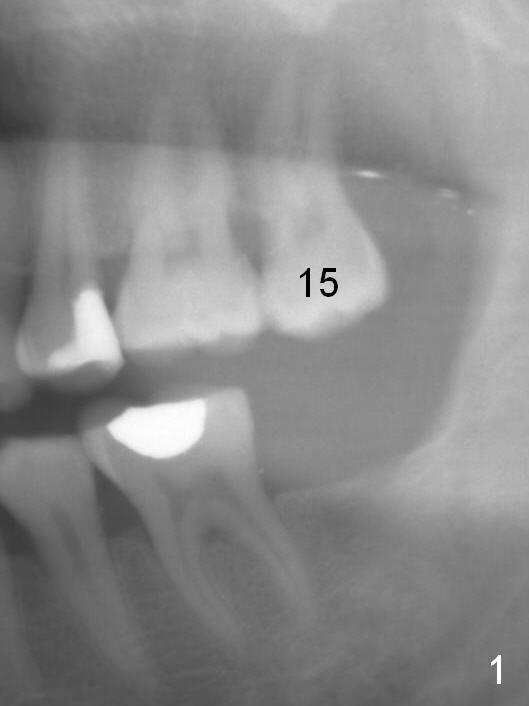

A 50-year-old man has lost the tooth #18 for 10 years; the opposing tooth (#15) has been supraerupted in the last 6 years (Fig.1,2). Mini-implants are placed to intrude the tooth #15 (Fig.2 arrow), instead leading to distalization in 4 months (Fig.3 arrow). Segmental orthodontic appliances are placed with noncompliance. Five months post implant placement at #18, a provisional (Fig.5 P) is fabricated with intentional supraocclusion. In 4 months, the marginal ridges of the teeth #14 and 15 are at the same level (Fig.4). To prevent the 2nd molar from distalization, keep the third molar if present.